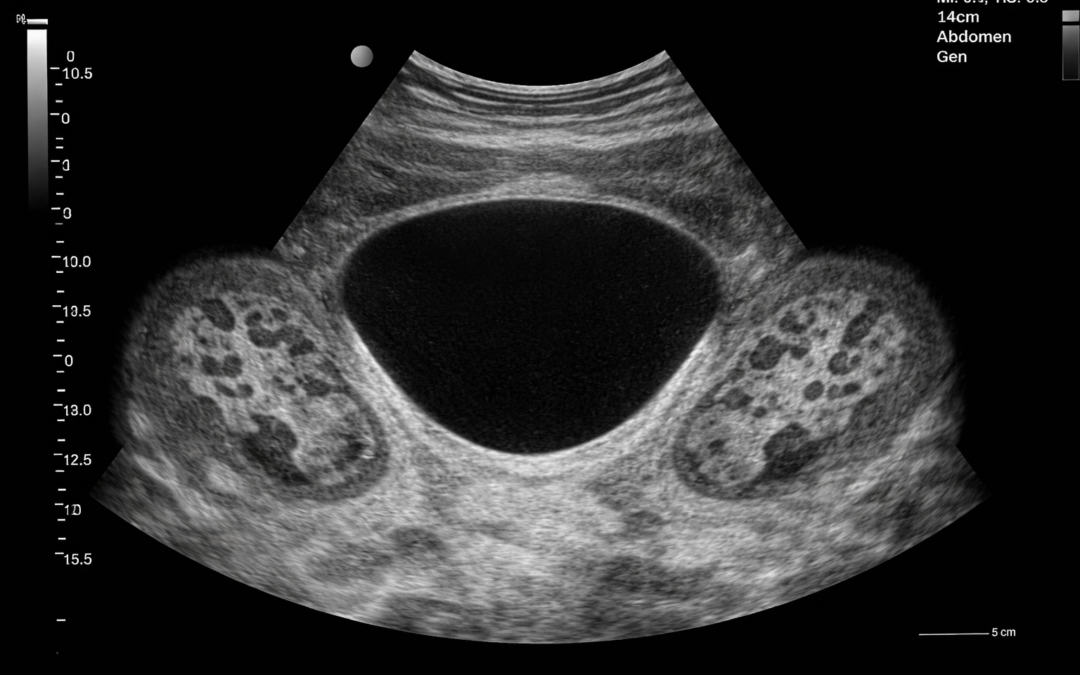

USG układu moczowego u Urolog Warszawa to badanie obrazowe, które pozwala ocenić budowę i wygląd narządów należących do układu moczowego. Najczęściej obejmuje ocenę:

- nerek,

- pęcherza moczowego,

- moczowodów w zakresie możliwym do uwidocznienia,

- zalegania moczu po mikcji, jeśli istnieje taka potrzeba.

Co może wykazać USG układu moczowego?

Badanie USG może pomóc w wykryciu różnych nieprawidłowości w obrębie układu moczowego. W zależności od sytuacji klinicznej może ujawnić między innymi:

- zastój moczu,

- poszerzenie układu kielichowo-miedniczkowego,

- kamienie w nerkach lub drogach moczowych,

- torbiele nerek,

- nieprawidłowości w budowie nerek,

- zaleganie moczu w pęcherzu po oddaniu moczu,

- zmiany wymagające dalszej diagnostyki.